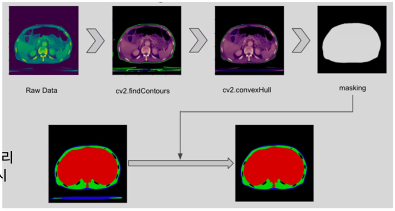

* Body Morphometry 경진대회

메모리의 한계를 극복하기 위해 Crop을 하고 Resize를 하여 타겟 부분만 학습을 하였다

추가로 noise 제거를 위해

cv2.findcontours , cv2.convexHull , masking을 순서 대로 적용을 함

저 find countour보면 밑에 초록색 밑줄 들이 noise로 작용함